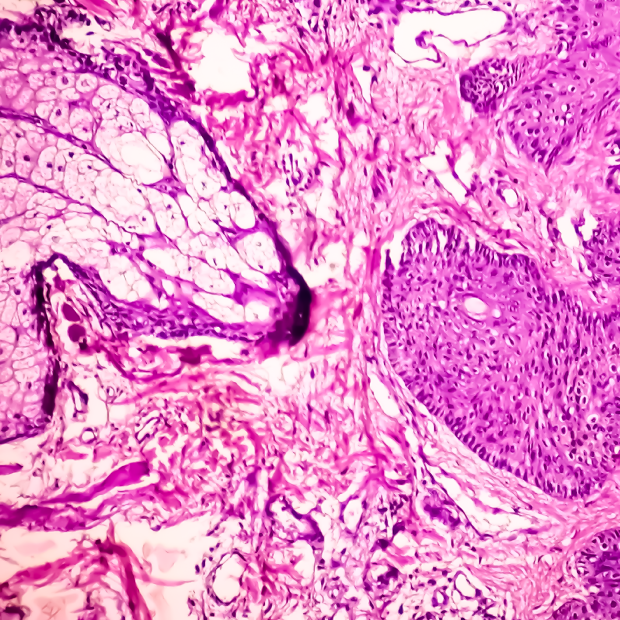

Sexually Transmitted Diseases (STD) is a general term for a variety of diseases transmitted through sexual behavior. There are more than 30 kinds of bacteria, viruses or parasites that may cause STDs, such as Chlamydia, Treponema pallidum, Trichomonas vaginalis, Human Papilloma Virus (HPV, may cause genital warts), Human Immunodeficiency Virus (HIV, may cause AIDS), etc., which may cause genital appearance lesions, increase the chance of cancer, develop symptoms of immunodeficiency, teratogenicity, or vertical transmission to the fetus. According to the statistics of the Taiwan Centers for Disease Control (CDC) in 2017, the top five notifiable infectious diseases are syphilis, tuberculosis, gonorrhea, HIV infection, and acquired immunodeficiency syndrome, including four STDs. In addition, hepatitis virus can also be transmitted through sexual behavior.

-HPV DNA Extraction Reagent Kits (61H series): It is applicable for HPV typing and can distinguish whether the HPV virus is high-risk type or low-risk type of cervical cancer.

- Grasp the processing and course of sexually transmitted diseases for cervical cancer diagnosis